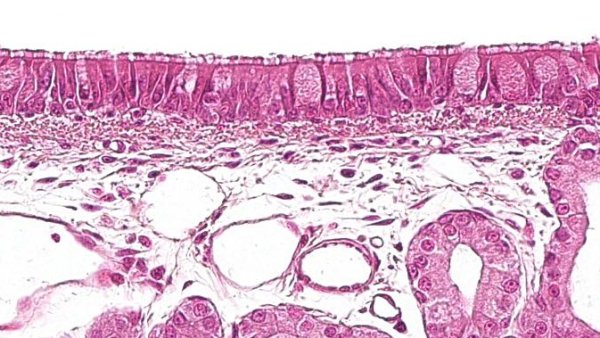

Welche Zellen bilden die Abwehrmechanismen des Atmungssystems beim Schwein? Wie sind sie angeordnet und wie kommunizieren sie miteinander?

Welche Zellen bilden die Abwehrmechanismen des Atmungssystems beim Schwein? Wie sind sie angeordnet und wie kommunizieren sie miteinander?